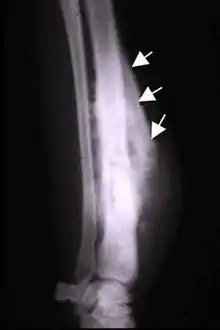

The Codman triangle (previously referred to as Codman's triangle) is the triangular area of new subperiosteal bone that is created when a lesion, often a tumour, raises the periosteum away from the bone.[1] A Codman triangle is not actually a full triangle. Instead, it is often a pseudotriangle on radiographic findings, with ossification on the original bone and one additional side of the triangle, which forms a two sided triangle with one open side. This two sided appearance is generated due to a tumor (or growth) that is growing at a rate which is faster than the periosteum can grow or expand, so instead of dimpling, the periosteum tears away and provides ossification on the second edge of the triangle.[2] The advancing tumour displaces the periosteum away from the bone medulla. The displaced and now lateral periosteum attempts to regenerate underlying bone. This describes a periosteal reaction.

The main causes for this sign are osteosarcoma, Ewing's sarcoma, eumycetoma, and a subperiosteal abscess.[3][4]